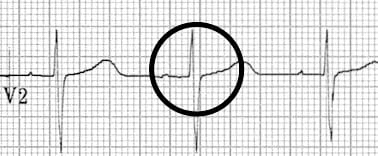

Bottom strip: Paroxysmal SVT. The P wave is seen as a pseudo-R wave (circled) in lead V1 during tachycardia. This very short ventriculo-atrial time is frequently seen in typical Slow-Fast AVNRT

- Pseudo R’ wave may be seen in V1 or V2